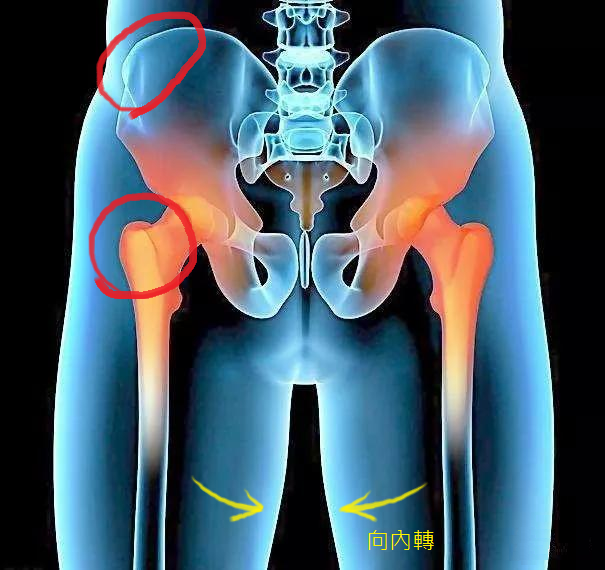

從下面這張髖部骨骼的圖片中,可以看到我們骨盆的位置有兩個關節點

一個是髖部的上端 (骨盆),一個在下端(大腿根部),想像如果下端那根大腿股骨向內轉(內旋),那麼就會讓上圖下端大腿根部的股骨更加突出,導致看起來臀部長在大腿根部的位置,大腿根部比臀部看起來還要寬,形成了梨形身材。

大腿骨尾端與骨盆連接的關節移位,也會造成梨形身材的體型;通常會發生在走路姿勢不正確、從小體弱的女生、或是懷孕時缺鈣的媽媽等等。股骨移位的樣子大概是像下圖:

這類梨形身材的人,有時候走路、下蹲或是做運動的時候,骨盆與大腿連接的問至會出現喀啦的聲音,因為股骨大轉子沒有完整的卡在骨盆的凹槽裡,無法好好的在正常軌道上活動與運動,到了一定的角度就會滑落、發出聲響。

判斷方法:用手觸摸大腿根部凸起的地方,如果摸起來是硬硬的骨頭,並且走路、運動的時候,骨盆處沒有喀啦喀啦的聲音,可以判斷為這一類的梨形身材。

判斷方法:用手觸摸凸起的大腿根部,如果摸起來是硬硬的骨頭,並且走路、運動的時候,骨盆處有喀啦喀啦的聲音,可以判斷為這一類的梨形身材。